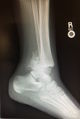

Salter Harris Types

Type 5 (Crush)

• Physis compression fx

• Typically occurs at knee or ankle

• May confuse for Type 1 injury

• X-ray findings may be minimal

• Highest chance of growth arrest

• Suspect based on mechanism of injury, joint effusion